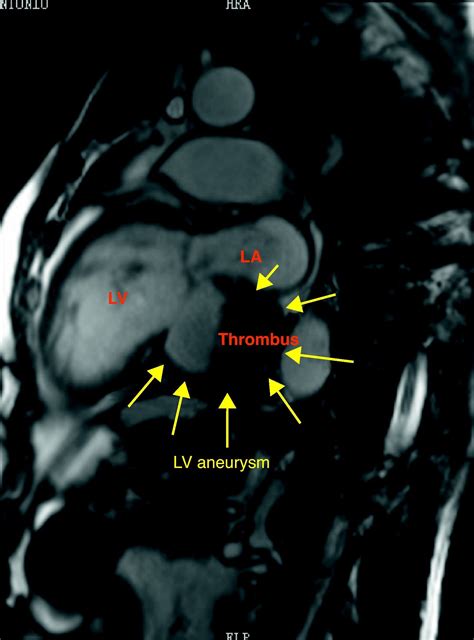

• Cardiac Magnetic Resonance Imaging (MRI): This provides detailed images of the heart and can help in diagnosing and assessing the severity of the aneurysm.

• Thromboembolism: Blood clots can form in the aneurysm and travel to other parts of the body, causing blockages in blood vessels.